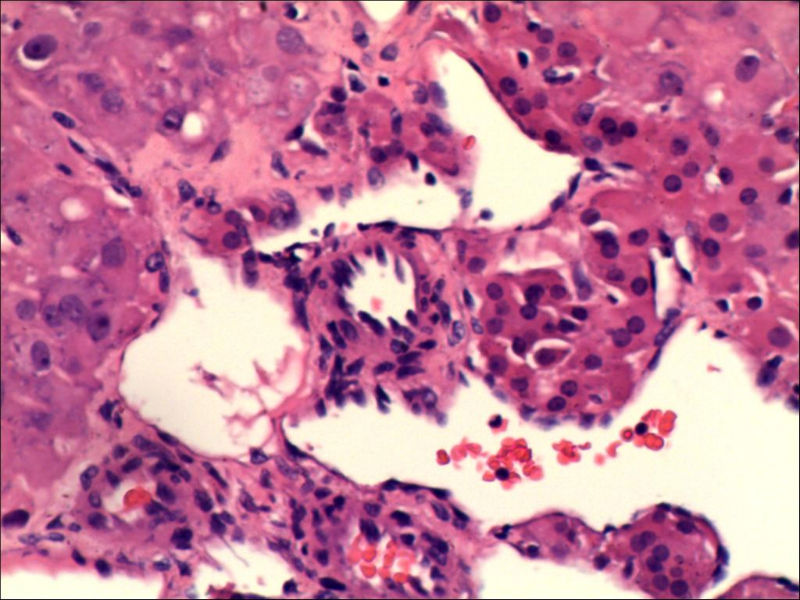

女,27岁,送检右侧卵巢肿物(另外还送检左侧卵巢肿物,大体及镜下显示为畸胎瘤),卵圆形,大小2×1×1cm,似有包膜。卵巢肿物图1

卵巢畸胎瘤中正常卵巢的黄体组织,铺砖样排列,胞浆宽大,较典型。

不好意思,可能是我没说清楚,患者对侧卵巢是畸胎瘤,不是同一侧的,我初步考虑门细胞瘤,图21,22,24,25,26中央的一些细胞是不是很像门细胞

其中一些大细胞怎么解释,建议在传一些中倍的图,图片有些暗了。

谢谢大家的回答和解疑,忘记一个重要的病史,就是该女性为产妇。但是妊娠黄体瘤与类固醇细胞瘤怎么鉴别呢

那应该是妊娠黄体/黄体瘤,类固醇细胞瘤有嗜酸细胞和组织细胞样细胞两种,此例显然不是。